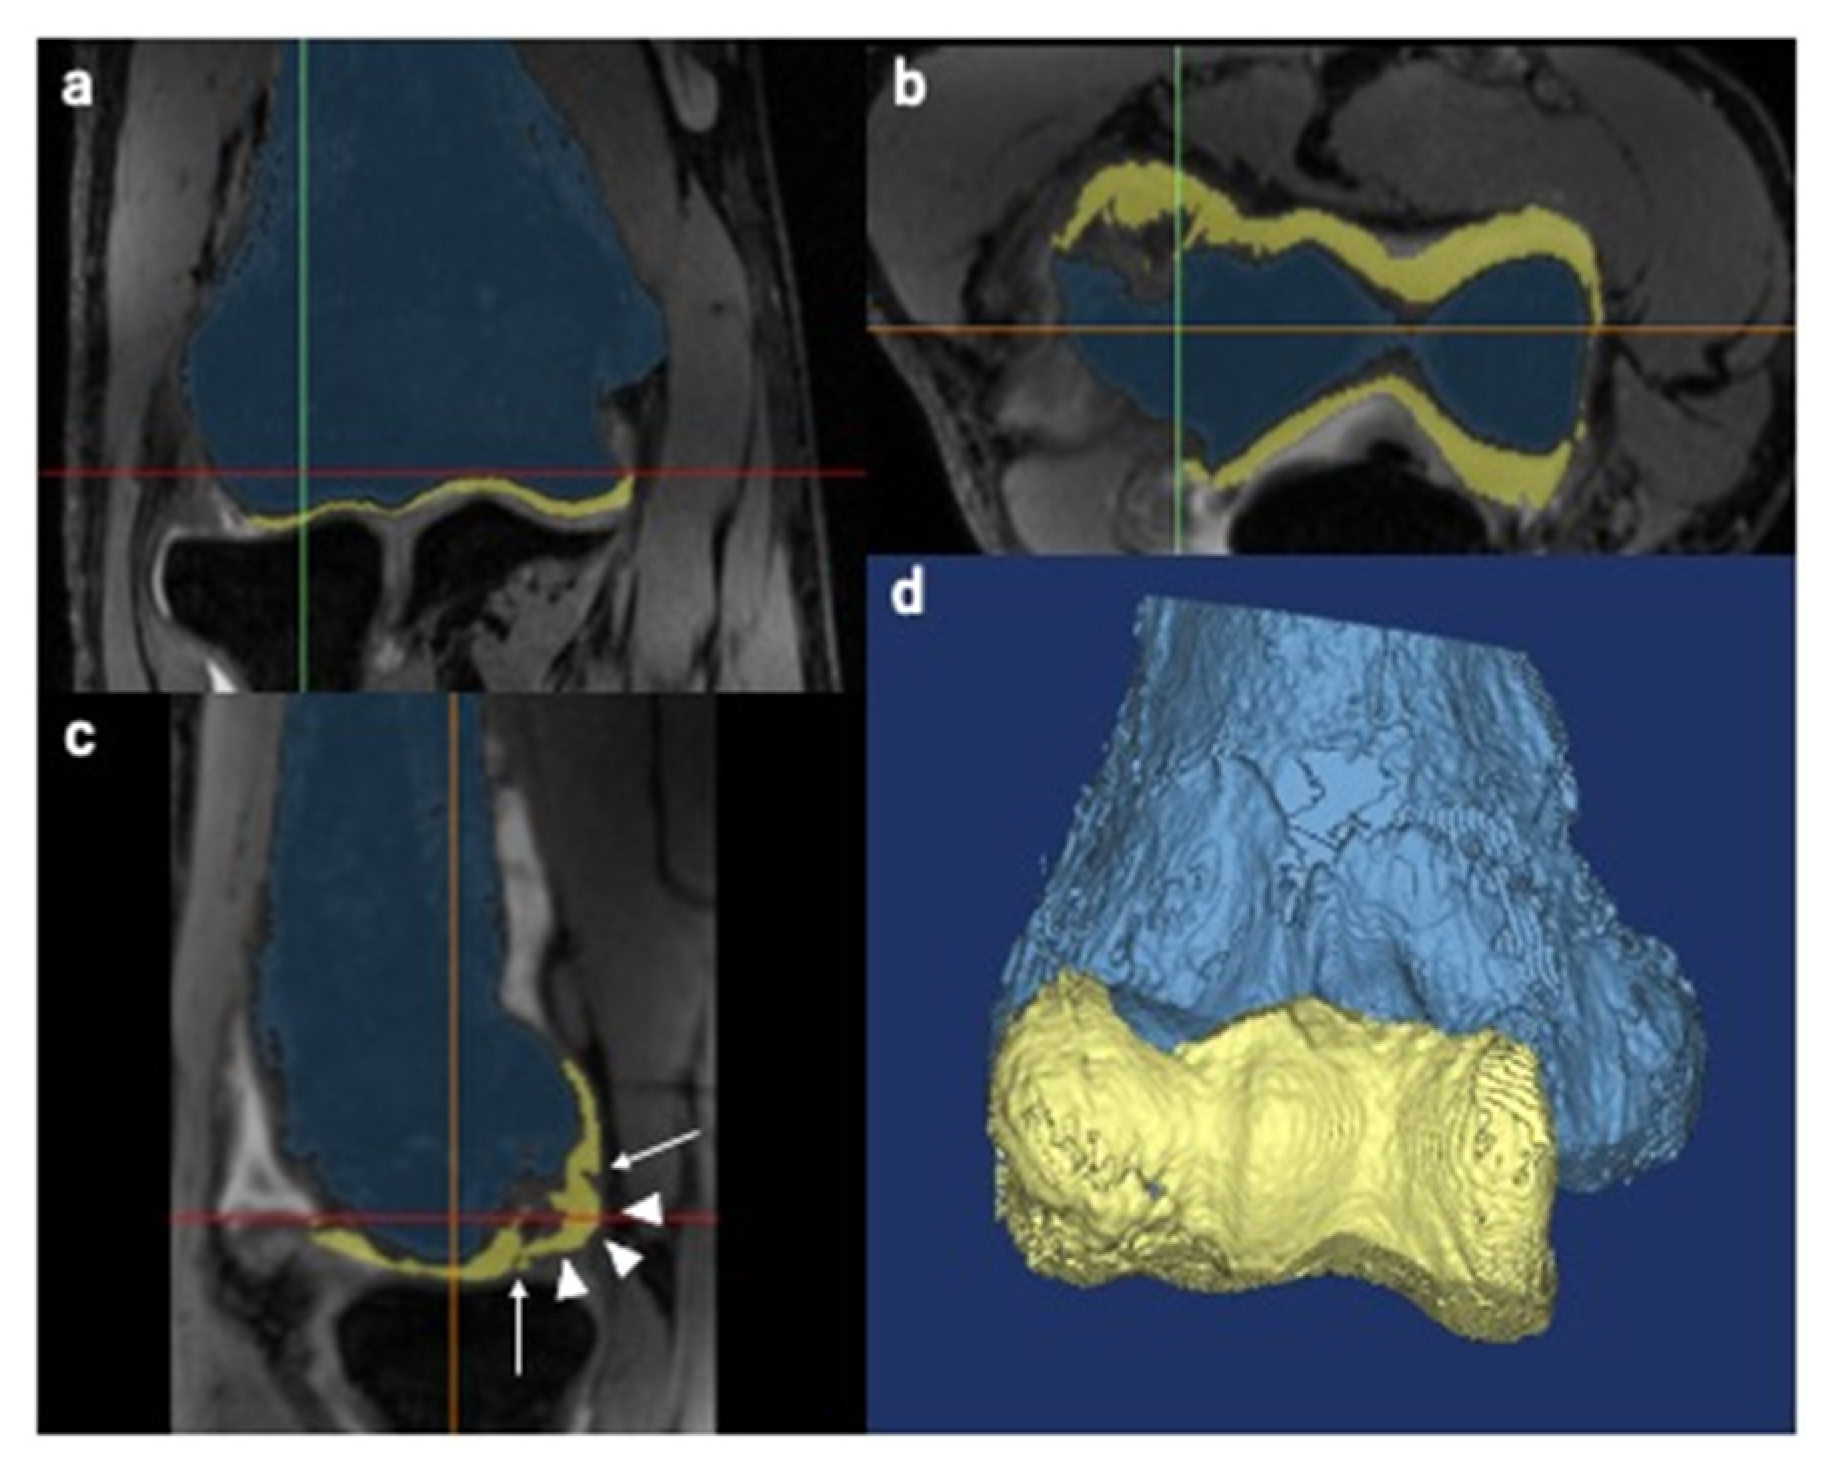

2.3. Creation of 3D Models

2.4. Fusion of Created 3D Models

2.5. Lesion Evaluation Using MCFIs